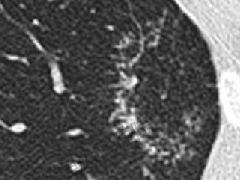

张力性纵隔气肿影像表现及严重度分级  迅速增大的肺部结节,首先考虑良性,确诊需要肺穿

迅速增大的肺部结节,首先考虑良性,确诊需要肺穿  肺隔离症:易误诊为肺癌的占位性病变,肺穿刺禁忌!